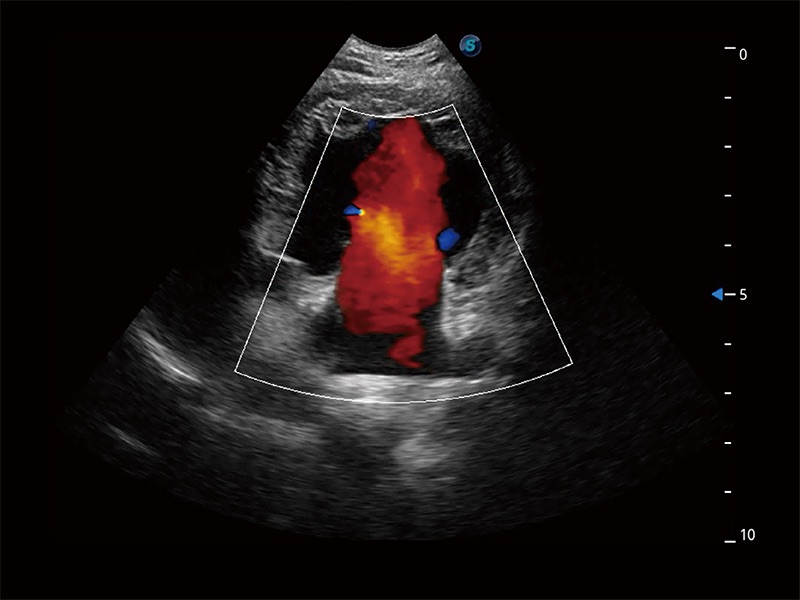

在傳統(tǒng)二維血流成像的基礎(chǔ)上,呈現(xiàn)血流的立體感,具有動感的生命力之美。即便是微小的血管也能輕松應(yīng)對,提高了血流的視覺敏感性。

ProPet 80 配備了豐富的心臟探頭群、先進(jìn)的成像技術(shù)和專業(yè)的心臟測量工具,可幫助動物醫(yī)生為不同體型和生理結(jié)構(gòu)的動物提供心臟和心肌功能的全面評估。